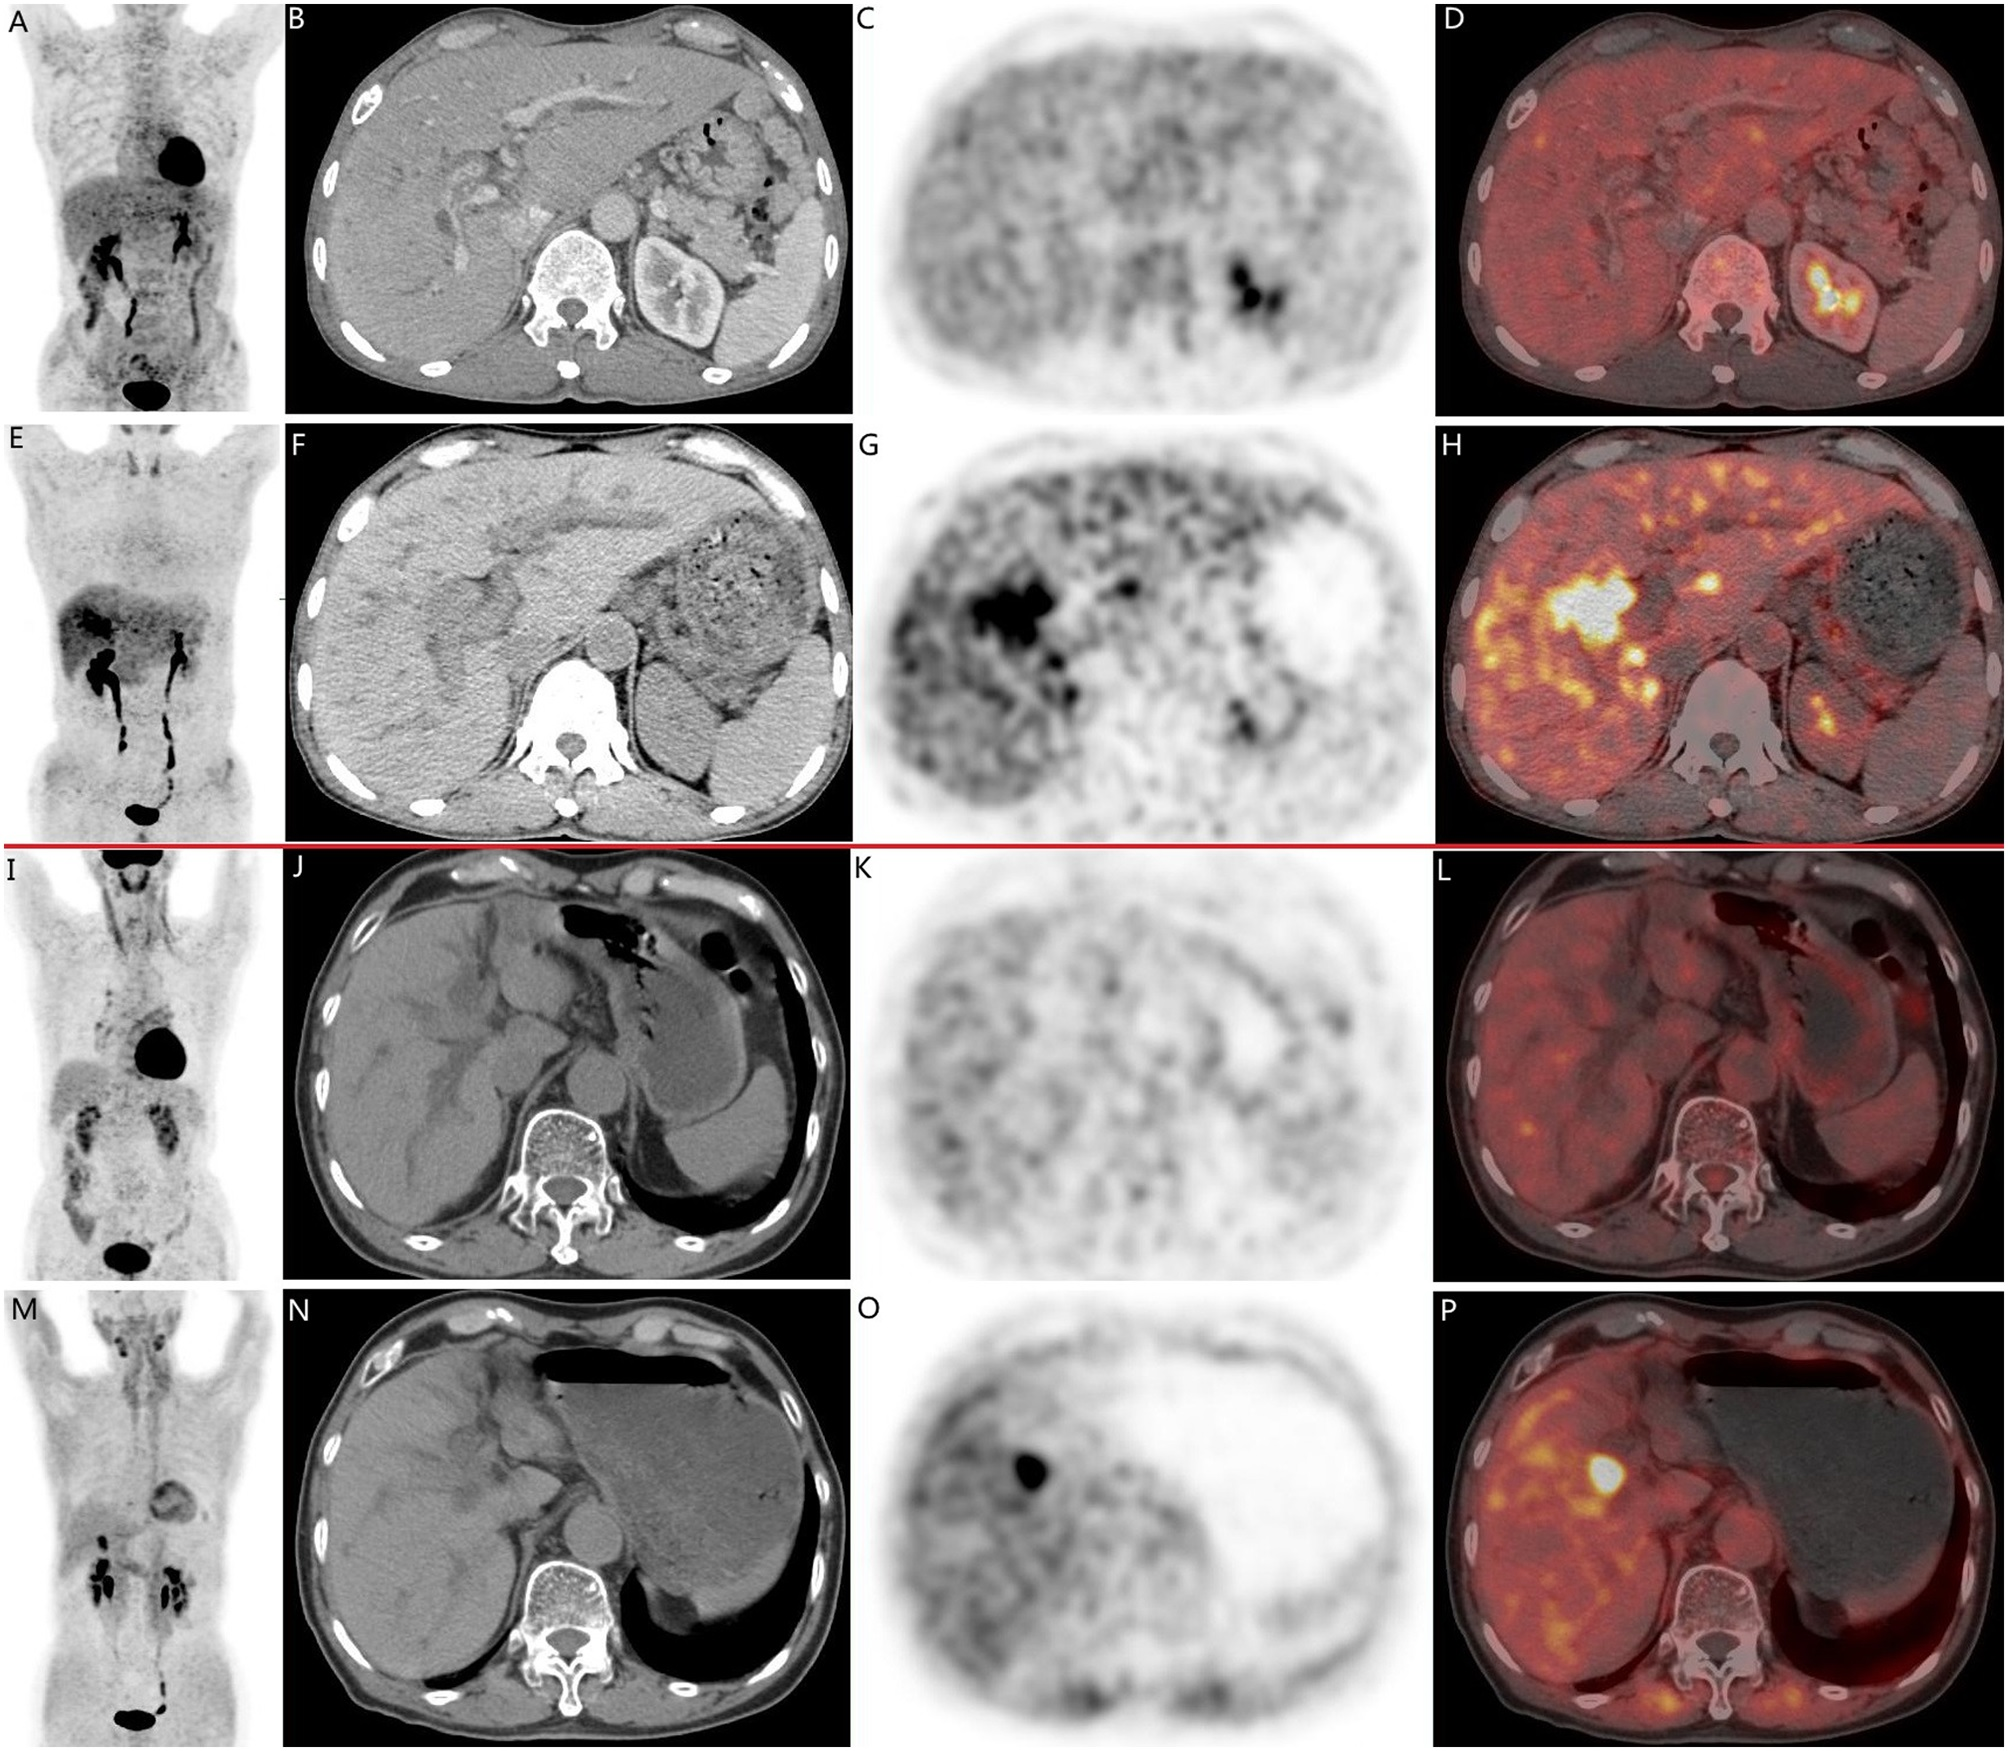

Typical PET (top), PET/CT (middle), and CT and MR (bottom) images of primary tumor obtained using both radiotracers in representative patients (A and B). Tumor is marked by arrows. DWI = diffusion-weighted imaging. Image courtesy of the Journal of Nuclear Medicine.

F-18 FAPI-04 PET/CT identified all patients with PDAC, while F-18 FDG-PET/CT missed one patient, according to the findings. F-18 FAPI-04 tracer uptake was higher than F-18 FDG in primary tumors (10.63 vs. 2.87, p < 0.0001), lymph node metastasis (2.9 vs. 1.43, p < 0.0001), and distant metastases (liver, 6.11 vs. 3.1, p = 0.002; peritoneal, 4.7 vs. 2.08, p = 0.015).

In addition, 14 patients were upgraded and one patient was downgraded due to F-18 FAPI-04 PET/CT scans compared with F-18 FDG-PET/CT, the authors noted.

“Our results demonstrate that F-18 FAPI-04 PET/CT is significantly superior to F-18 FDG- PET/CT in detecting both primary and metastatic lesions,” the researchers wrote.